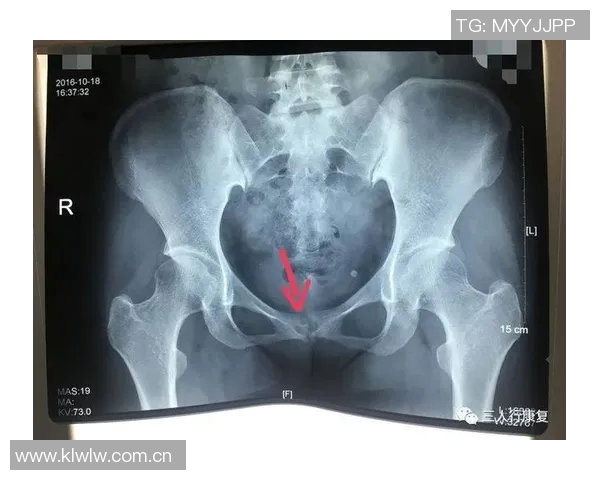

耻骨炎是一种常见于运动员中的损伤,尤其是在进行高强度训练或比赛时更为普遍。它主要表现为耻骨区域的疼痛和不适,通常伴随着活动能力下降。在运动中,特别是涉及到快速变向、高强度跑动等动作时,疼痛感会更加明显,这使得许多运动员无法正常发挥。

此外,耻骨炎还可能导致局部肿胀和压痛,使得患者在日常生活中也遭遇困扰。这种疼痛不仅限于身体运动,还可能延伸至心理方面,例如焦虑和沮丧,因为持续的不适感限制了他们参与喜爱的体育活动。

对于亚马尔这样一位优秀的足球运动员来说,耻骨炎无疑对他的职业生涯造成了严重威胁。他需要在赛场上不断展现爆发力,而疼痛则让他难以做到这一点。因此,了解其基本概念和症状,对于及时诊断与干预具有重要意义。